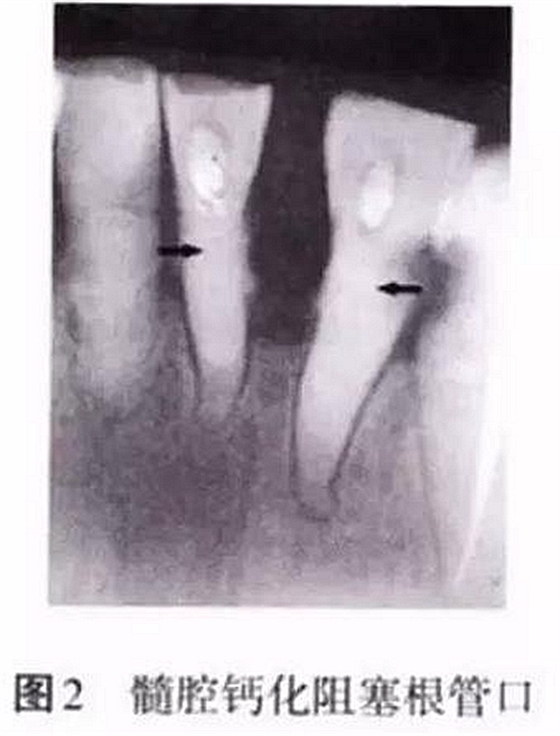

髓腔的形態(tài)非一成不變,年齡的增長、外界物理和化學(xué)刺激、齲損等都會引起髓腔形態(tài)的改變,如髓腔體積變小、髓室頂和底的距離減小、髓腔鈣化阻塞根管口等,都會增加開髓難度(圖2)。術(shù)前如檢查不充分,未考慮髓腔的生理病理變化,并采取相應(yīng)的治療措施,常會導(dǎo)致在尋找根管口的過程中破壞髓室底,甚至出現(xiàn)穿孔。